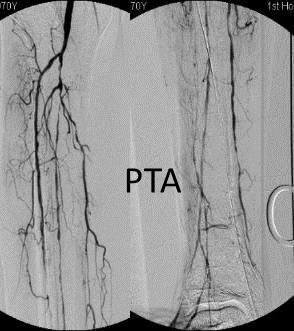

各分支 CTO 解剖特点

三大主要分支的CTO近端与远端常见位置:

总体特点:

膝下通常有单个或数个可见的流入道;

病变常为单个或多个CTO组合,总长度可达20cm;

部分患者存在踝上交通动脉或完整的踝下足底弓,为逆向开通提供可能。